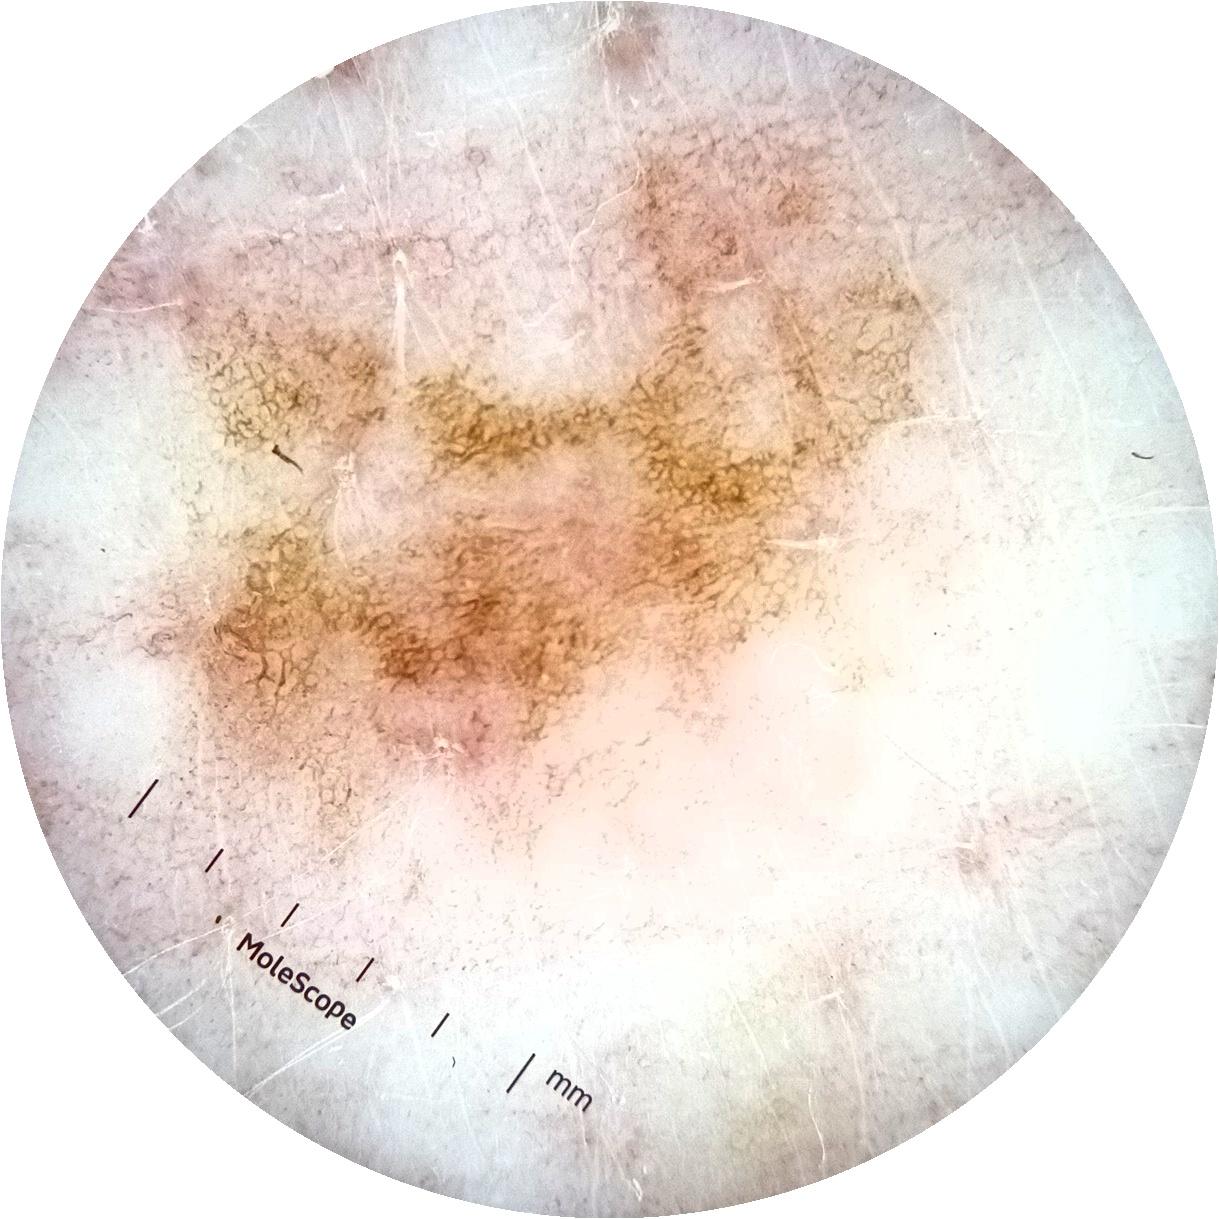

ISIC_3754278

acquisition_day 135

age_approx 65

anatom_site_1 Upper extremity

diagnosis_1 Benign

diagnosis_confirm_type single image expert consensus

fitzpatrick_skin_type I

image_type dermoscopic